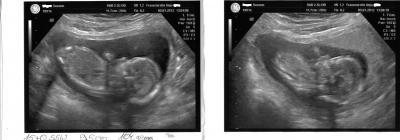

Hallo Ihr lieben, nach dem ich mit Termin heut 3 STUNDEN !!!warten musste habe ich noch erfahren das Sie keinen Ultraschall macht ok dachte ich mir dann Bezahle ich halt hauptsache ich seh mein Baby Gesagt getan meinem Baby geht es super es hat Geschlafen aber sowas von Süss das glaub ihr garnicht. Er ist 9,5 cm "groß" und 104 gramm "schwer". Sie hat auch noch mal gesagt das er (warscheinlich) ein Junge wird. ich bin heute 15+0 ssw laut untersuchung 15+2 ssw. Ach Mädels ich freu mich so das mit meinem Baby alles ok ist aber ein wehmutstropfen gab es noch ich habe 1,6 kg zugenommen ich habe gefragt ob das ok ist und sie sagte ja beim 2 kind nimmt man schneller zu na toll das macht mut so jetzt möchte ich euch nicht weiter stören. ich hänge euch noch die Bilder von heute an lg und einen schönen abend

Bild zu Bericht vom Frauenarzt + Fotos - Forum für Juni - Mamis

Super das freut mich das alles In Ordnung ist,ja mann sieht auf dem Bild das es eindeutig ein Junge ist. Ich freue mich sehr für dich...... Liebe Grüße Melanie